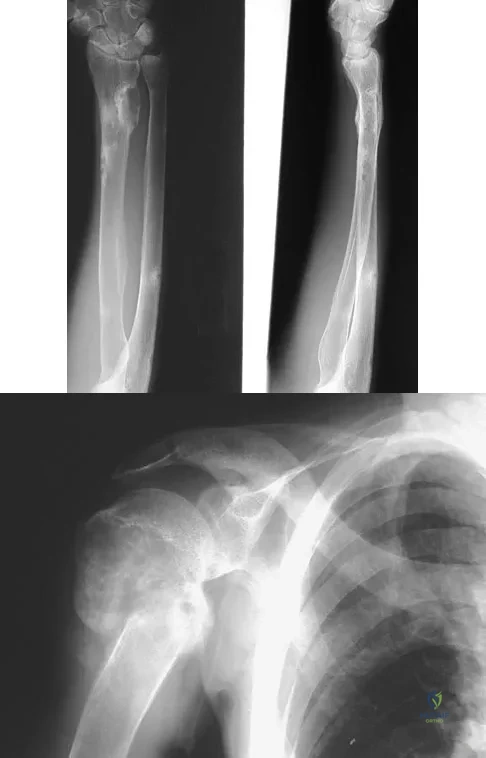

A 33-year-old man reports an enlarging painful soft-tissue mass in his right forearm. A radiograph and MRI scans are shown in Figures 45a through 45c. Treatment should consist of

An 11-year-old boy sustained an injury to his arm in gym class. He denies prior pain in the arm. Radiographs are shown in Figures 48a and 48b. What is the next most appropriate step in the management of this lesion?

An 8-year-old boy is diagnosed with acute onset cauda equina syndrome. A radiograph, MRI scans, and a biopsy specimen are shown in Figures 57a through 57d. What is the most appropriate treatment?